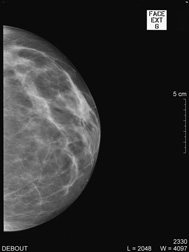

| Debout, le sein légèrement comprimé, deux clichés sont réalisés de face et en oblique sur chaque coté ; d’autres clichés localisés pour mieux analyser une zone peuvent aussi être effectués. |